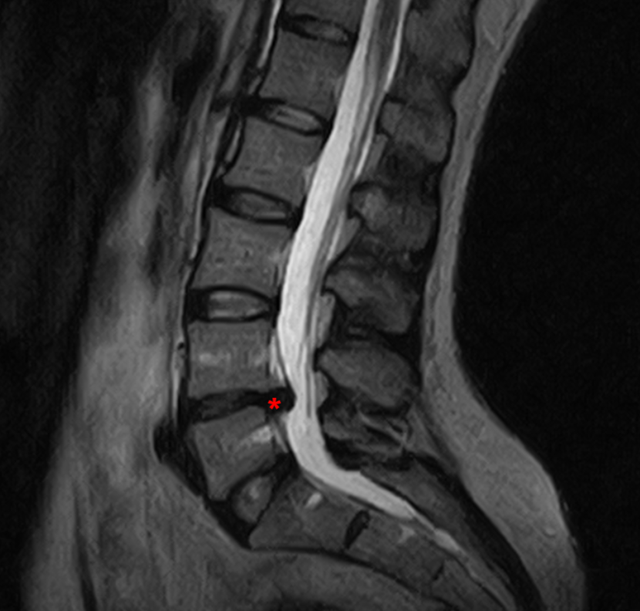

A livello cervicale il disco più coinvolto è a C5-C6, a livello lombare a L4-L5. È proprio a questo livello che sono più frequenti le ernie del disco ed in generale qui è più frequente la patologia degenerativa: disco nero, artrosi e stenosi. Ci si chiede come proteggere e preservare l’integrità dei dischi vertebrali.. Diversi fattori possono causare il mal di schiena, ma nella maggior parte dei casi esso è collegato alla degenerazione dei dischi intervertebrali (IVD). Lo sviluppo di nuove tecniche di coltura cellulare, la progettazione di polimeri biocompatibili e strategie di ingegneria dei tessuti sono recentemente emersi come opzione terapeutica nella.